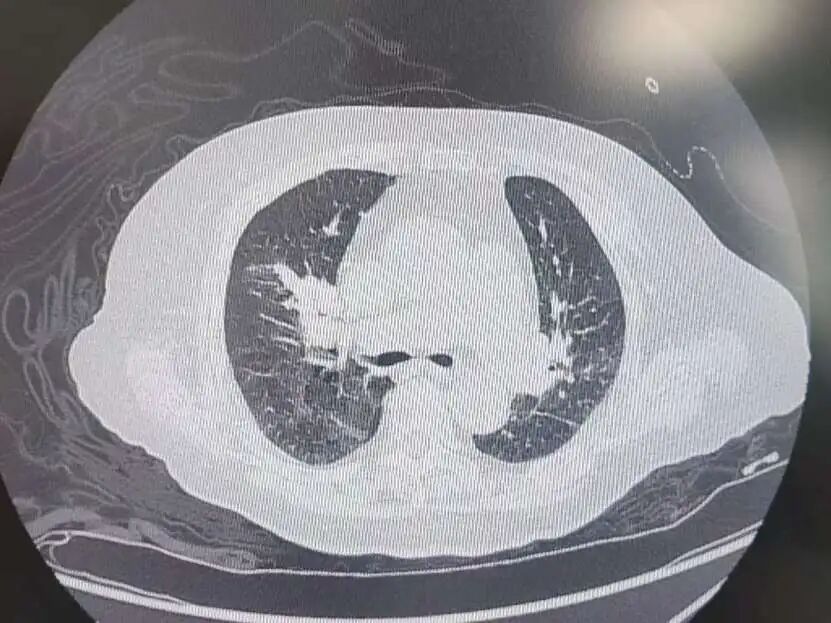

患者高血压病史7年,最高血压达190/100mmHg,2型糖尿病7年,控制不佳。发病前3天,意外摔伤致股骨颈骨折,后出现咳嗽、呼吸困难、胸痛等症状,被紧急送到我院急诊。完善相关检查后,明确诊断为中高危肺栓塞——这是一种足以危及生命的急症,病情进展迅速。

肺占位

为进一步精准救治,呼吸与危重症医学科宋刚主任带领团队对患者进行全面评估,结果令人揪心:肺血栓栓塞(中高危)、I型呼吸衰竭、肺占位性病变、急性冠脉综合征、急性肾功能不全、肝功能不全、脓毒症等多种疾病,且随机血糖高达31.68mmol/L,远超正常范围,生命体征岌岌可危。